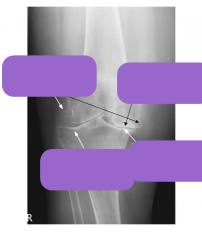

What do the labels show?

What is the underlying pathology

osteoarthritis